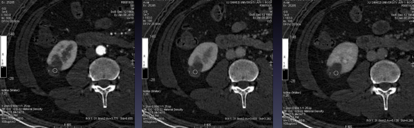

病史:男性,50岁 扫描参数: Mode:GSI -22 375mA@0.7sec/rot@DC40mm@SFOV Body Large Pitch:0.984:1 造影剂注射方案:300mgI/100ml@60ml@4ml/sec;Smartprep 病例分析过程: 1. 下图是横轴位5mm平扫及三期强化图像,参与病例讨论的医生半数以上认为有强化;病灶是肯定的,讨论的焦点是有无强化,这是判断病灶性质的关键。